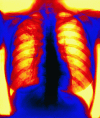

Community based approaches to the control of multidrug resistant tuberculosis: introducing "DOTS-plus"